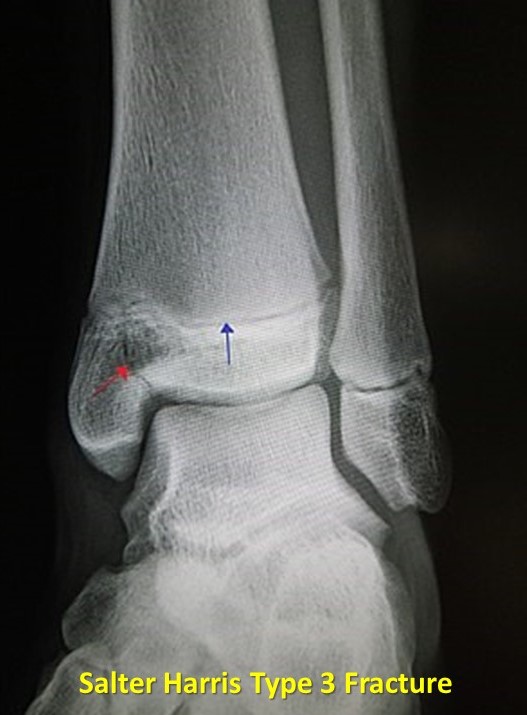

Salter-Harris Fracture Classification